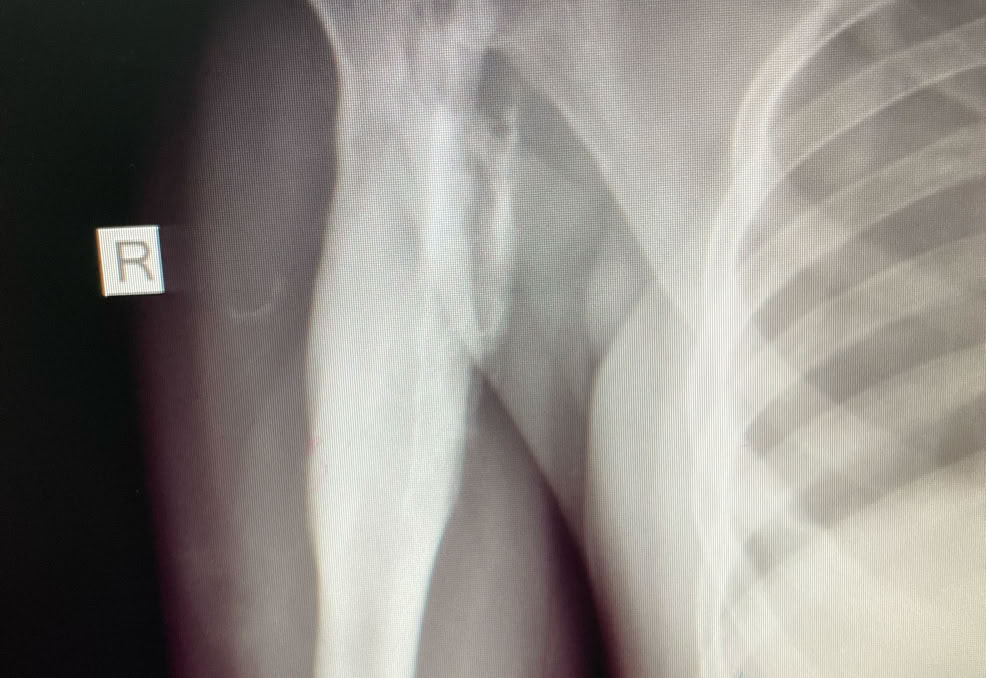

Hemos operado dos casos de osteomielitis crónica. Una en la tibia de un adolescente de 15 años y otra en una joven de 18 años en el húmero.